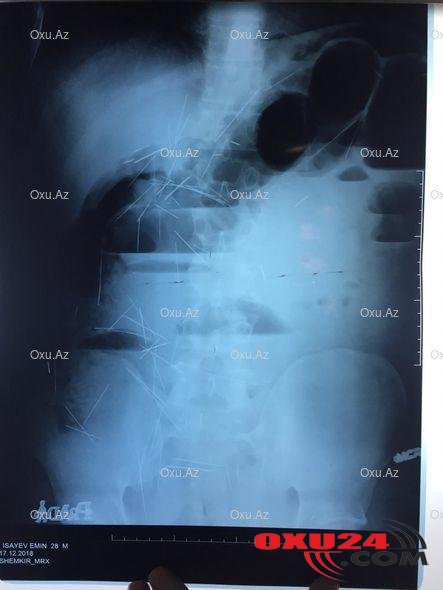

Oxu24.com-un əldə etdiyi məlumata görə, rayon sakini, 28 yaşlı İsayev Emin ayın 17-də Şəmkir Mərkəzi rayon Xəstəxanasına müraciət edib. O bildirib ki, mədəsində narahatlıq hiss edir. Xəstənin müayinəsi zamanı MRT (Maqnit rezonans tomoqrafiya) çəkilib və məlum olub ki, onun mədəsində, bağırsaqlarında 200-dən çox tikiş iynəsi var. Xəstənin həyati təhlükəsi olduğunu düşünən həkimlər onu dərhal Bakıya Respublika Klinik Xəstəxanasına göndəriblər. Hazırda onun xəstəxanada olduğu deyilir. Faktla bağlı Səhiyyə Nazirliyinin mətbuat xidmətinin rəhbəri Pərviz Abubəkirov Oxu.Az-a verdiyi açıqlamasında bildirib ki, həmin şəxs xəstəxanaya özü müraciət edib: "Həmin şəxs özü çox rahat şəkildə xəstəxanaya gəlib. Bildirib ki, bir müddətdir narahatlıq hiss edir. Həkimlər nə ilə bağlı narahatlıq duyduğunu soruşduqda, onlara bir iynə udduğunu deyib. MRT çəkilişi zamanı həkimlər gördükləri görüntüyə inana bilməyiblər. 28 yaşlı xəstənin mədə və bağırsaqlarında 200-dən çox iynə olduğu aşkarlanıb. Professorlar hadisənin necə baş verdiyini anlamağa çalışırlar. Bu insanın sağ qalması möcüzədir". P.Abubəkirov onu da əlavə edib ki, həkimlər xəstənin psixoloji problemləri olduğunu təsdiqləyəcək rəy çıxara bilmirlər: "Xəstə ilə bütün profillərdən olan həkimlər görüşüb. Hazırda psixoloqlar, psixiatrlar onunla söhbət edir. Həkimlər xəstənin verilən bütün suallara adekvat və normal cavablar verdiyini deyir. Xəstədən bu iynələri nə üçün udduğu soruşulub. O deyir ki, artıq iki ildir iynə udur. Onun sözlərinə görə, yuxarıdan ona vəhy gəlib ki, hər gün müəyyən miqdarda (6-7 ədəd) iynə udsun. Xəstənin əməliyyat olunması olduqca risklidir. Hazırda həkimlər bu istiqamətdə nə edə biləcəklərinə dair iclas keçirir, fikir mübadiləsi aparır. Xəstə iki ildir bu vəziyyətlə yaşayır. Əməliyyat zamanı onun ölmə ehtimalı böyükdür. Xəstənin ailəsi xəstəxanaya gəlib və onu evə aparmaq istədiklərini deyiblər. Həkimlər onun vəziyyətini ailəsinə izah etməyə çalışsalar da, ailəsi israrla bütün məsuliyyəti öz üstlərinə götürdüyünü deyərək onu evə aparıblar".